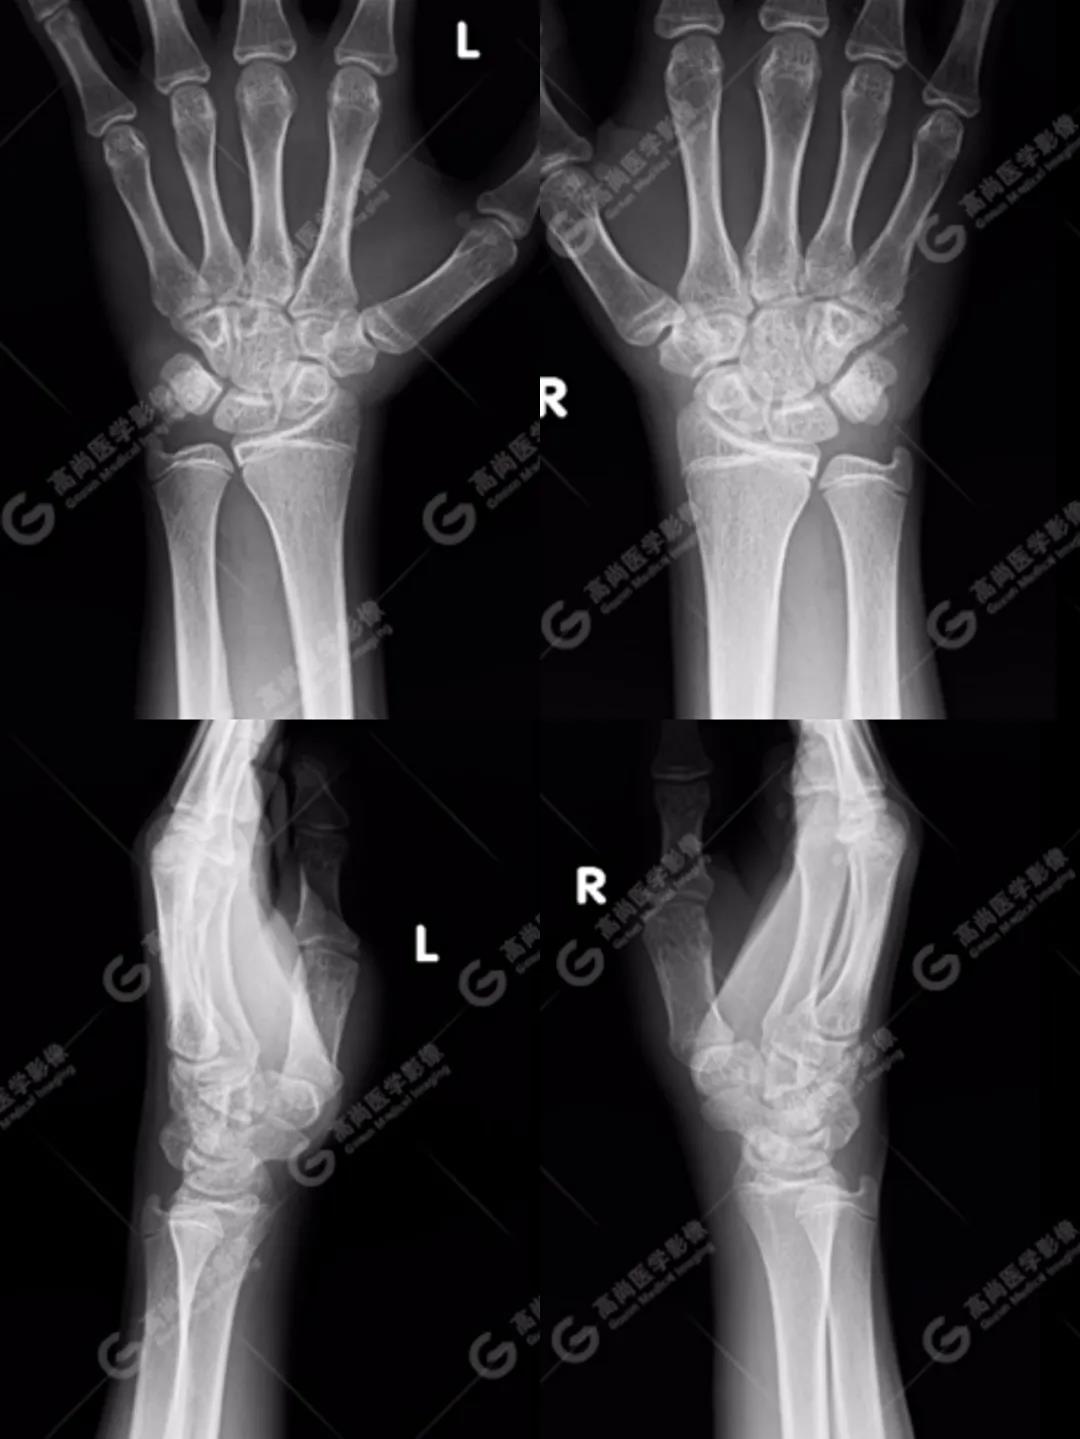

病史摘要 14歲男性,雙側(cè)腕部摔傷1天,雙側(cè)腕關(guān)節(jié)周圍壓痛,右手握拳乏力,按壓疼痛明顯,關(guān)節(jié)活動無明顯受限,體格檢查無明顯骨摩擦感;經(jīng)過一天后疼痛無明顯改善,遂來高尚醫(yī)學(xué)影像診斷中心行相關(guān)檢查。

1、雙腕關(guān)節(jié)正側(cè)位平片

按照臨床診療的常規(guī)思路,遇到這種情況首先行X線平片攝影檢查(老百姓通俗講的“照片”)。

如下圖所見:雙腕關(guān)節(jié)諸骨未見明顯骨折征象。

沒有看到明顯的骨折線,患者的疼痛是不是軟組織損傷造成的、回家擦一些紅花油之類的外用藥就ok了的“小問題”呢?考慮到孩子即將面臨考試,家長還是不放心,擔(dān)心X線影像重疊等因素造成漏診,想進一步明確,提出進行CT檢查(由于成像原理的差別,CT對于細微骨折的顯示要明顯優(yōu)于常規(guī)X線攝影)。